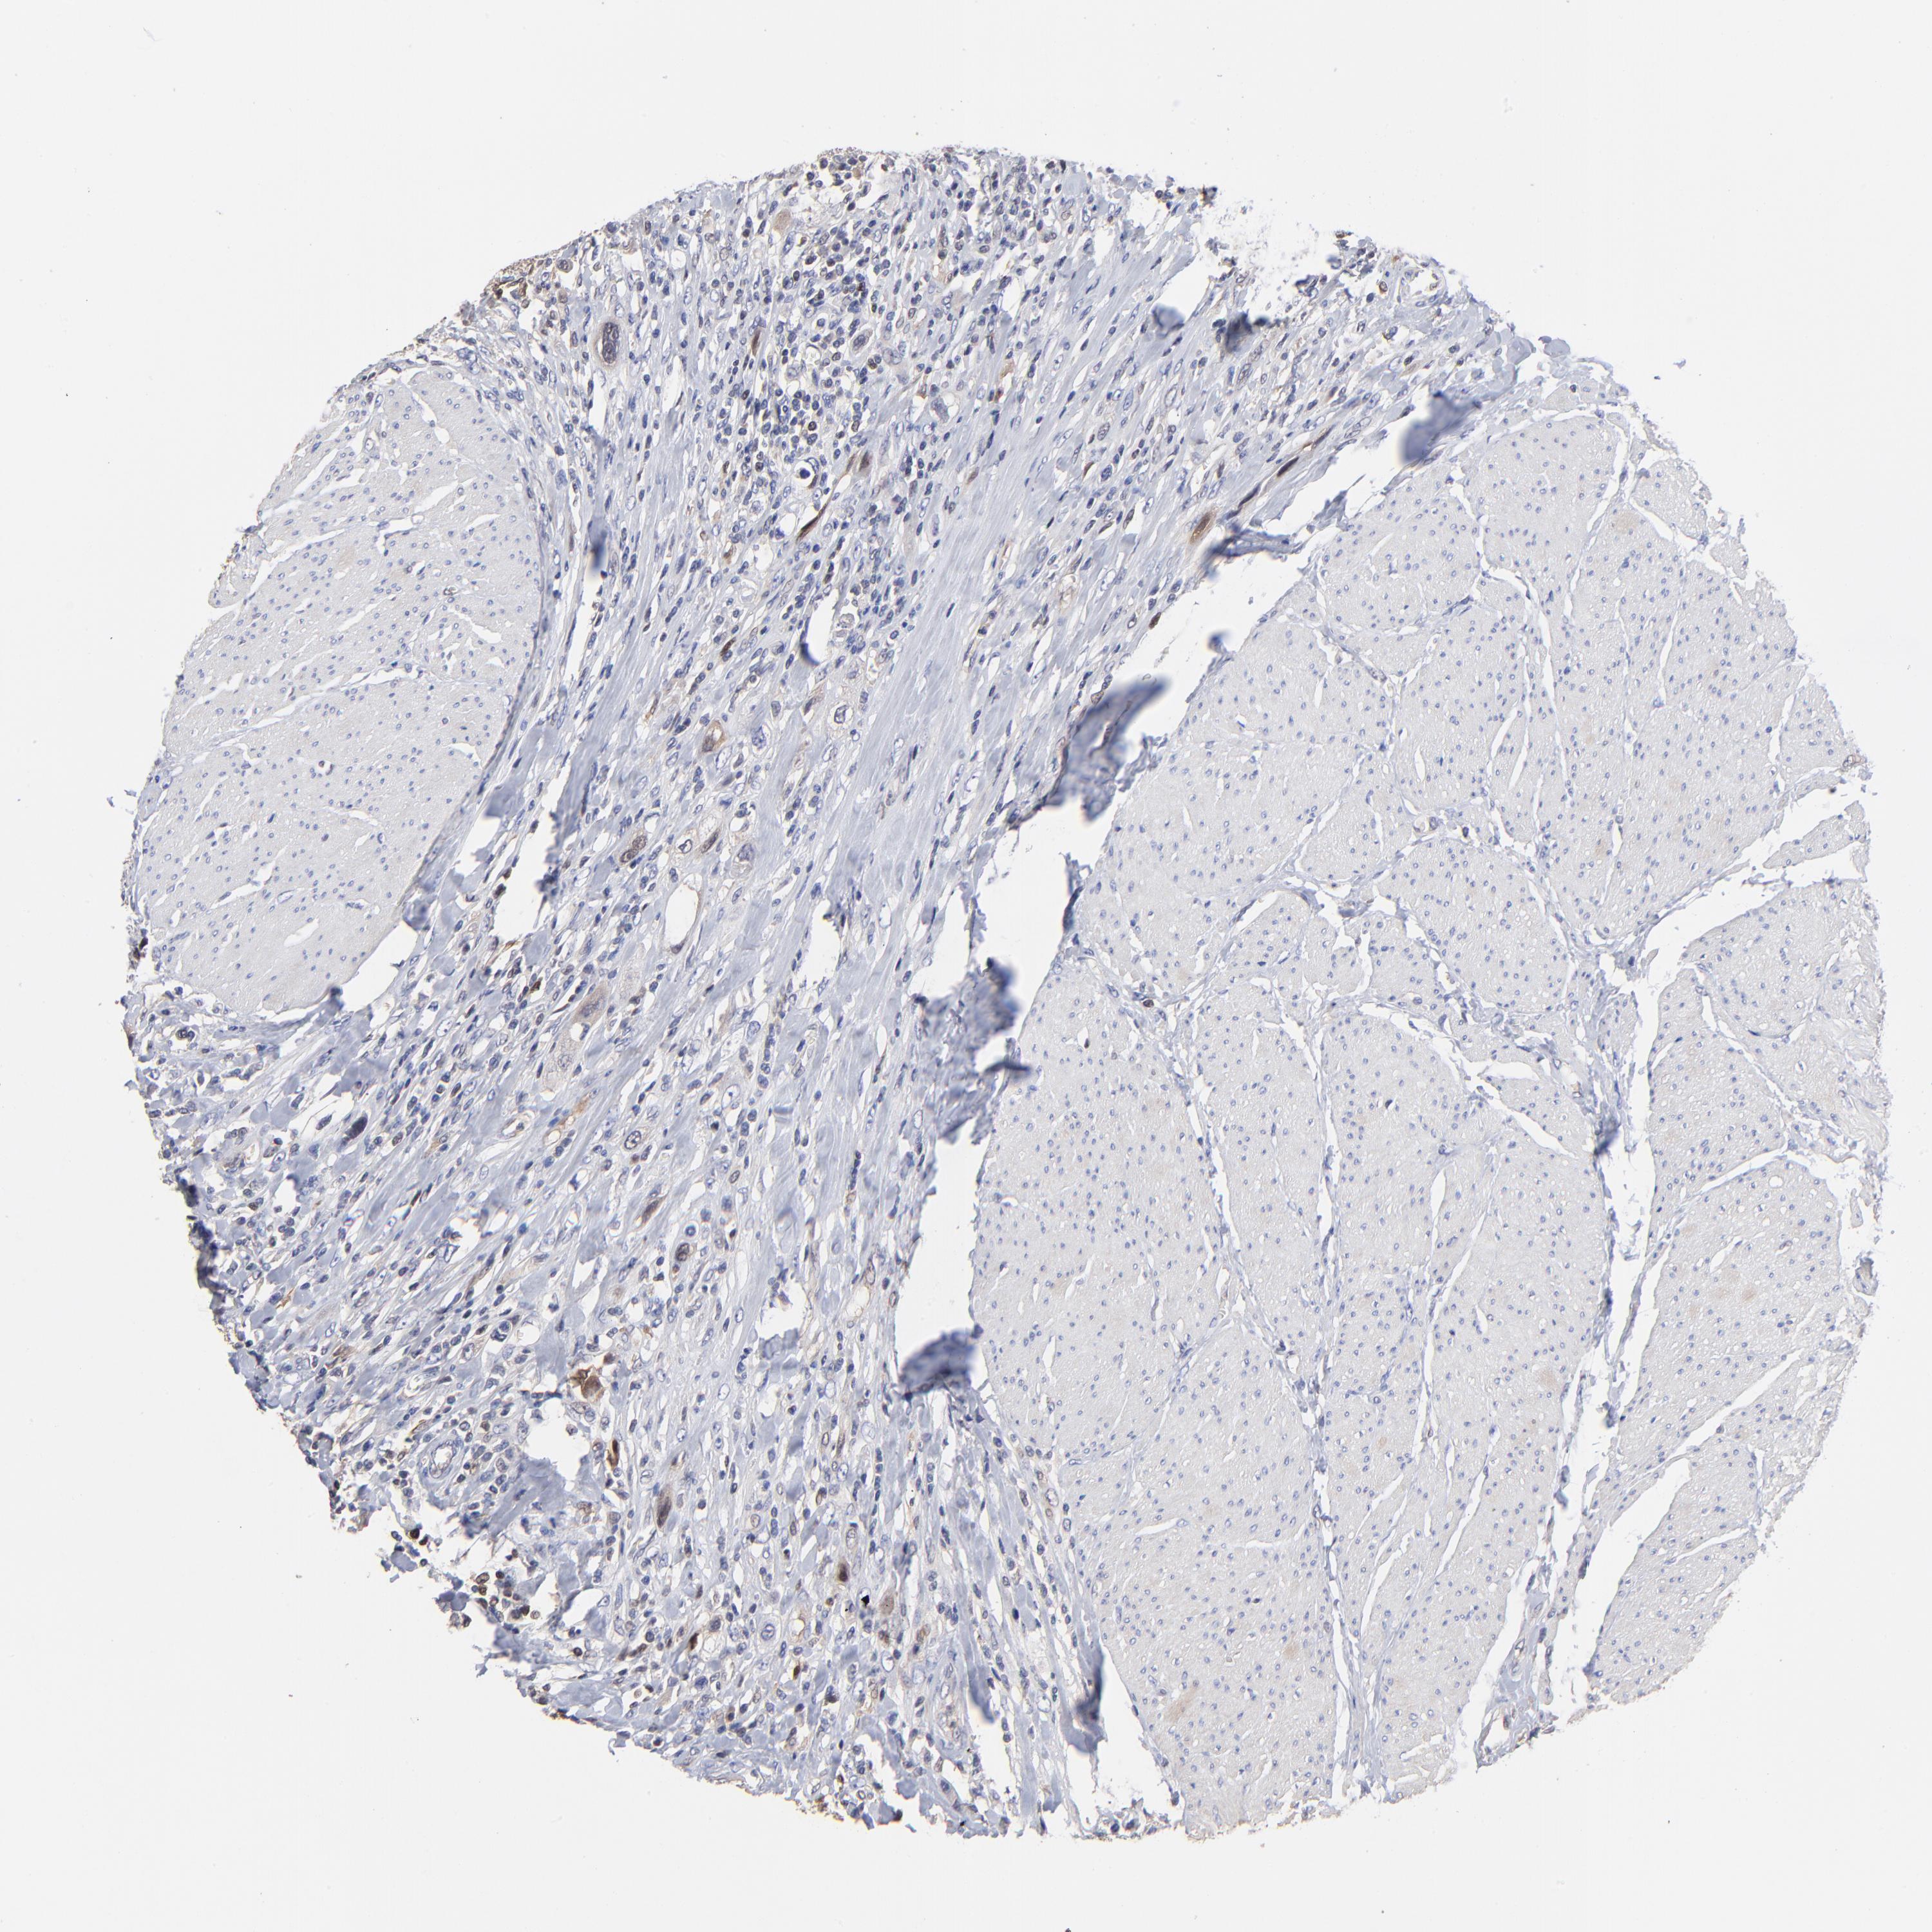

UROTHELIAL CANCER - Protein expressioni

A mouse-over function shows sample information and annotation data. Click on an image to view it in a full screen mode. Samples can be filtered based on level of antibody staining by selecting one or several of the following categories: high, medium, low and not detected. The assay and annotation is described here.

Note that samples used for immunohistochemistry by the Human Protein Atlas do not correspond to samples in the TCGA dataset.

Antibody stainingi

Antibody staining in the annotated cell types in the current human tissue is reported as not detected, low, medium, or high, based on conventional immunohistochemistry profiling in selected tissues. This score is based on the combination of the staining intensity and fraction of stained cells.

Each image is clickable and will lead to virtual microscopy that enables deeper exploration of all samples and also displays staining intensity scores, fraction scores and subcellular localization as well as patient and tissue information for each sample.

Antibody HPA002832

Staining

High

Medium

Low

Not detected

Intensity

Strong

Moderate

Weak

Negative

Quantity

>75%

75%-25%

<25%

None

Location

Nuclear

Cytoplasmic/membranous

Cytoplasmic/membranous,nuclear